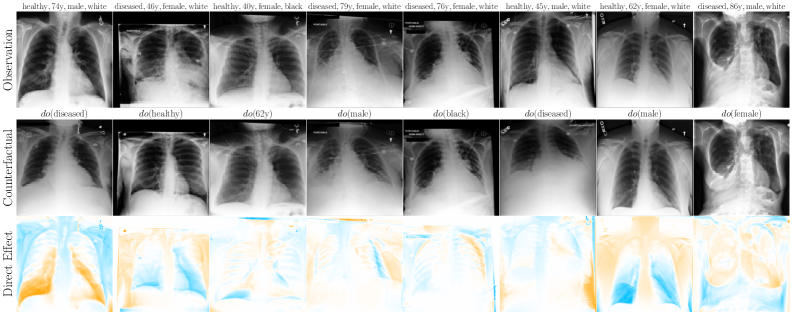

6.2 Case Study: Chest X-ray Imaging Counterfactuals

To extend our study to high-dimensional settings, we conduct experiments on MIMIC-CXR (Johnson et al., 2019), a widely used dataset for counterfactual inference. Our assumed causal graph follows the baselines (Ribeiro et al., 2023; Xia et al., 2024), and includes Sex (), Race (), Age () and Disease () variables, where , and cause the X-ray image . To parameterise our flow models, we use a streamlined version of Dhariwal and Nichol (2021)’s UNet architecture (see Appendix F for details). Table 2 and Figure 4 report our main results. We observe substantial improvements over baselines (Ribeiro et al., 2023; Xia et al., 2024) using our flows, across all three counterfactual soundness axioms, and without requiring any costly counterfactual fine-tuning or classifier(-free) guidance. That said, this alone does not imply causal validity. In Appendix F, we report additional comparisons and ablations. We observe performance trade-offs: for instance, OT-Flow (which assumes Markovianity) outperforms on race interventions but underperforms Flow on disease interventions, suggesting non-Markovian interaction effects or a subpar OT approximation. Notably, our Markovian OT coupling substantially improves over the Naive OT flow baseline.